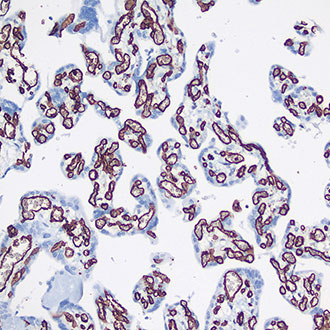

CD31

CD31 -